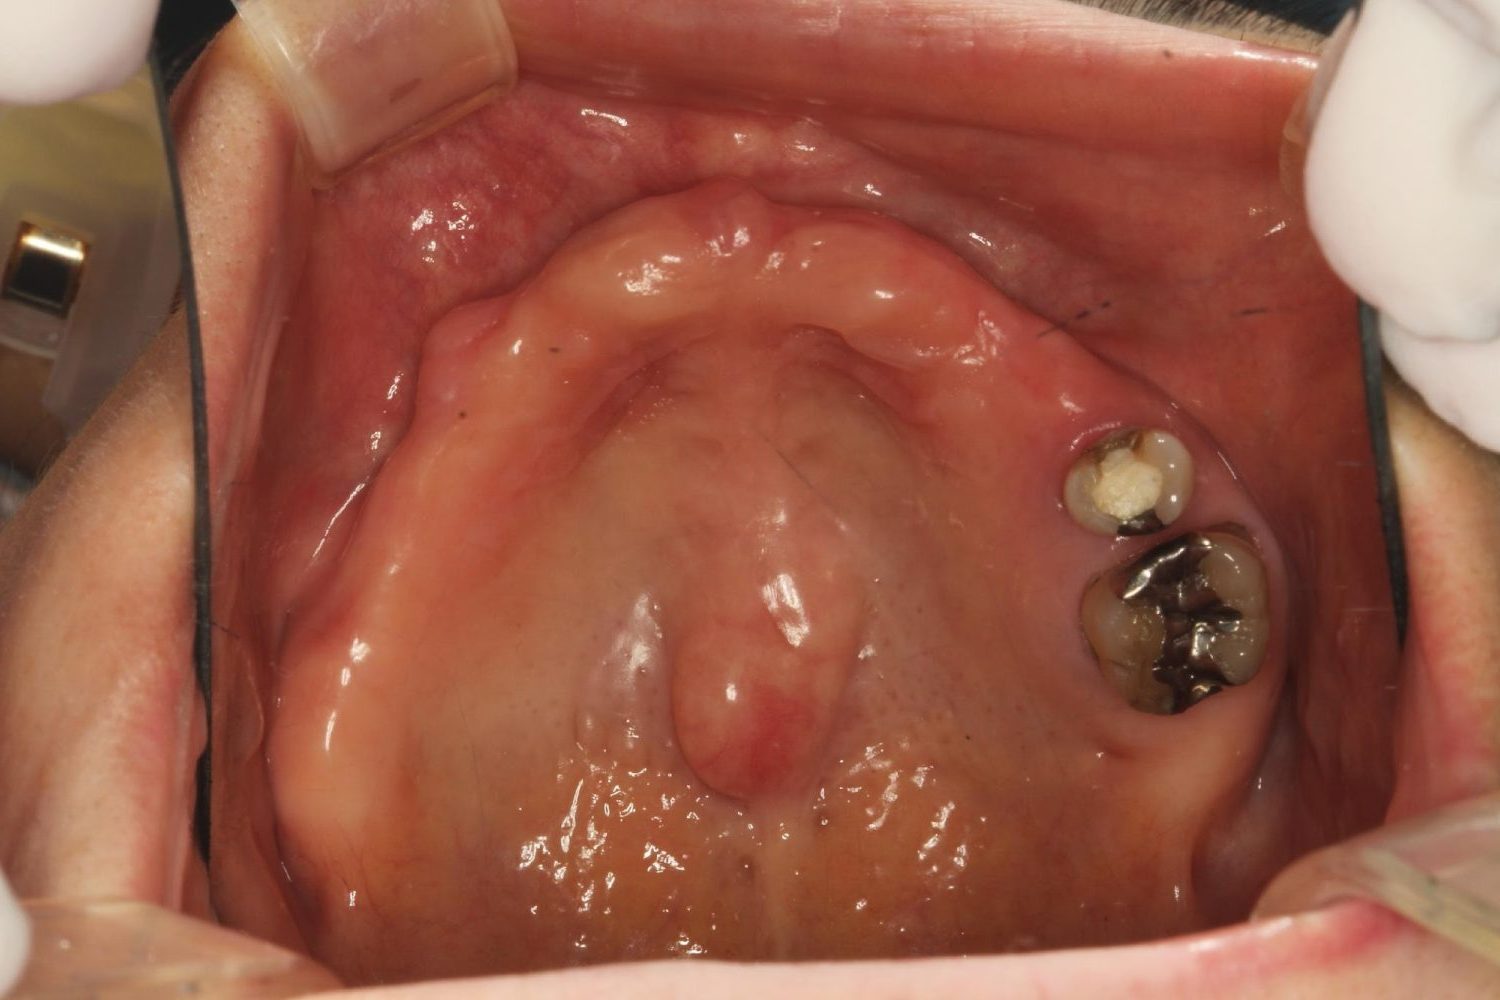

インプラント治療の症例紹介③

Before

After

主訴

むし歯の治療

治療内容

保存不可能な歯の抜歯

下顎にインプラント埋入し咬合再構成

治療費

2,688,400円(税込)

治療期間

14か月

治療回数

21回

想定されたリスク

※上部構造の形態が複雑になるため清掃が難しくなる。インプラント周囲炎の恐れがありました。

多数歯う蝕および多数歯欠損による咬合崩壊、保存不可能な歯の抜歯により上下無歯顎に。下顎に6本インプラント埋入する事で咬合再構成を行った。